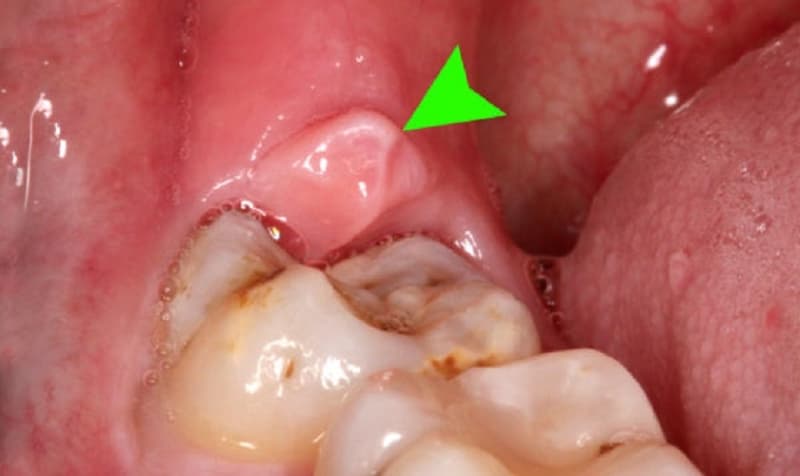

Viêm nướu răng trong cùng khiến nướu bị sưng đỏ, đau nhức, ảnh hưởng sinh hoạt hàng ngày

– Nướu răng đỏ và sưng: Nếu nướu răng bị viêm, màu sắc thường hồng nhạt sẽ chuyển sang màu đỏ hoặc đỏ tím. Tình trạng này có thể kèm theo sưng to.

– Ứ đọng mủ và dịch: Sự viêm nhiễm khiến nướu răng không còn chắc chắn bám vào chân răng. Điều này sẽ dẫn đến sự ứ mủ và dịch, thậm chí có thể gây xung huyết.

– Răng bên cạnh đau nhức: Sưng nướu răng có thể làm cho các vùng xung quanh cảm thấy đau nhức. Đồng thời, nướu bị viêm có thể ảnh hưởng, gây ra đau rát cổ họng và khó chịu khi ăn uống.